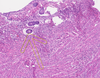

1

Q

Name of the Slide?

A

Senile Endometrial Atrophy

2

Q

Name of the Detail:________?

A

Atrophic Gland